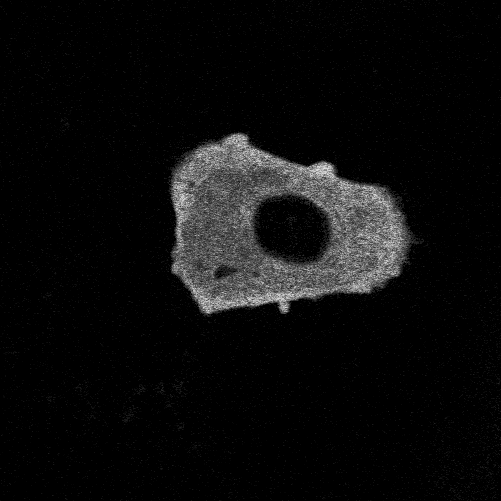

To study glioblastoma, we use glioblastoma organoids: three-dimensional spheres created from patient tumour tissue that contain not only the malignant cells but also immune cells, non-tumour glial cells, and other components of the tumour environment. This model is better at predicting how a tumour will respond to treatments compared to traditional cell cultures.

To study the interactions we are engineering a better model in which these organoids also contain neurons so that we can study how the interactions between tumour cells and neurons promote tumour progression and so that we may identify ways to intervene and prevent tumour cells from integrating into brain networks.